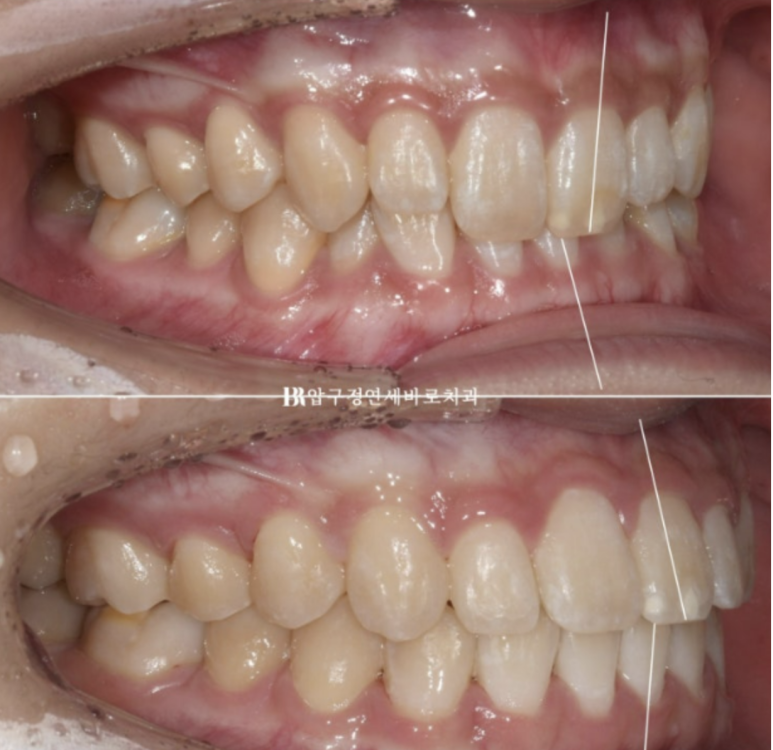

앞니 각도가 정상으로 회복이 되면서

22.07~23.11

옥니가 얼마나 개선이 되었을까요?

옥니 과개교합이 개선되면서

2022,07~23.11

뒤로 말려들어가 있던 입술에 입체감이 생기고 입매가 예뻐졌습니다.

교정으로 아래턱이 뒤로 들어간 것은 아니지만

입술 볼륨이 회복이 되면 주걱턱으로 보이던 것도 개선이 됩니다.

또 다른 치료 목표였던 앞니 노출도 개선으로 미소도 더 좋아졌습니다.